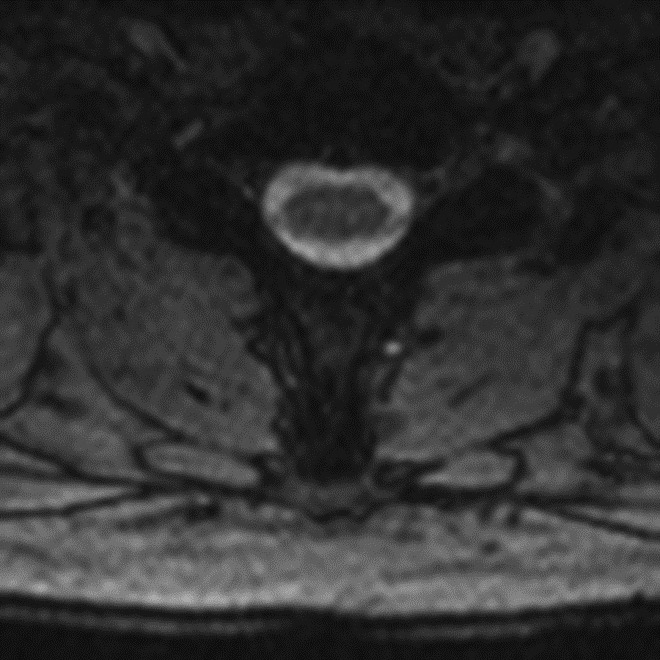

Pulsation Artifact. Axial T2-weighted fat-saturated MR image of the pelvis demonstrates femoral artery pulsation resulting in ghost images (arrowheads) obscuring the anterior labra and simulating femoral head lesions bilaterally.